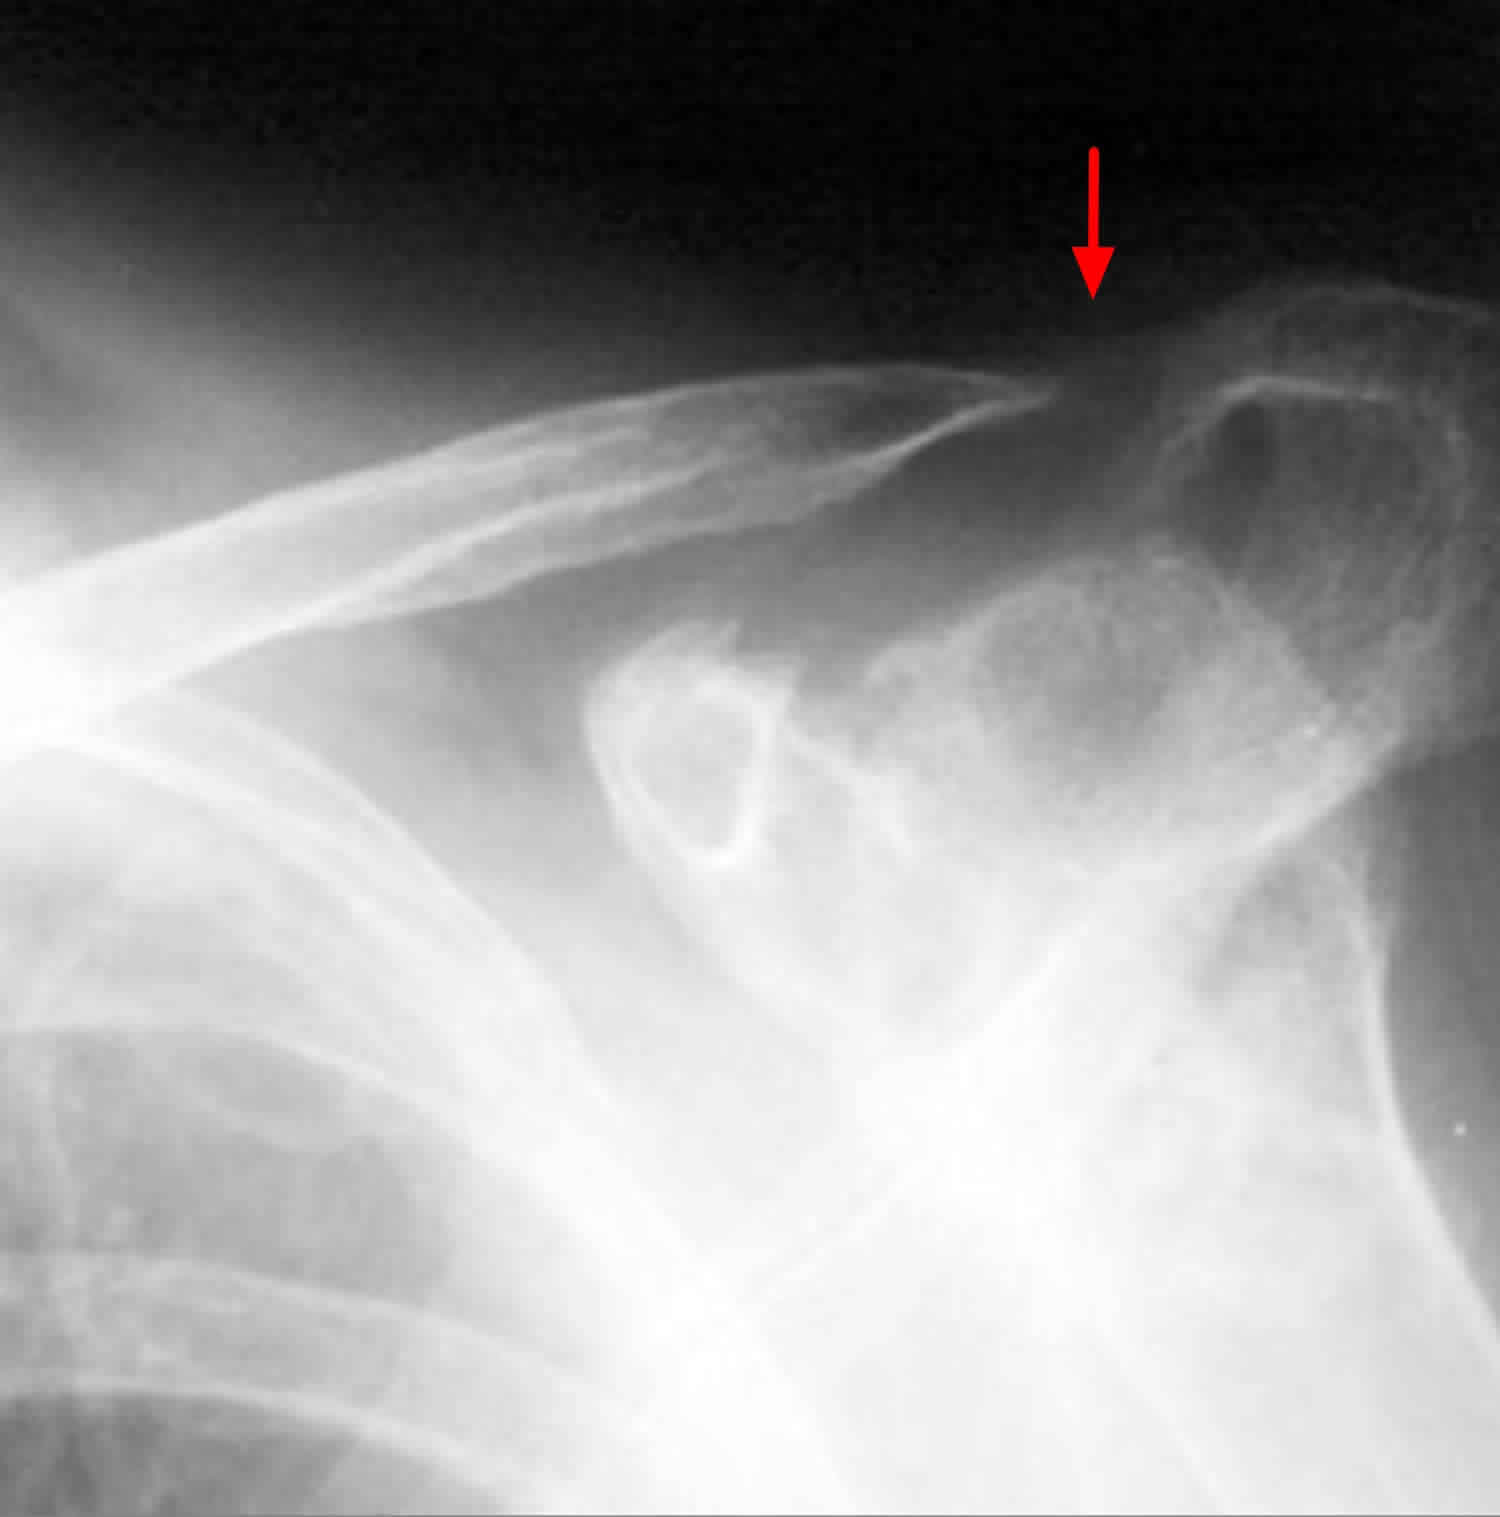

When you take a child to the emergency department for a suspected buckle fracture radius, the physician will perform a physical examination followed by an X-ray. It is important to note that because the fracture is a compression rather than a gap, it can sometimes be difficult to see on an X-ray unless the image is taken from exactly the right angle.

Radiologists look for a small "kink" or cortical disruption on the distal radius. Sometimes, a subtle thickening of the cortex is the only diagnostic clue. If the initial X-ray is inconclusive but the clinical suspicion remains high, doctors may recommend a follow-up visit or immobilization as a precautionary measure.